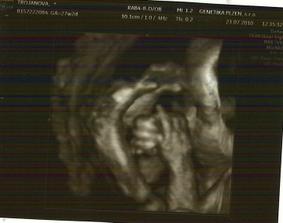

23.7.2010 jdeme na 3D ultrazvuk 🙂 - 27tt+2

3D ultrazvuk byl prostě bomba, všechno nám pan doktor zkontroloval

takže máme 34cm a 1,4kg a máme všechno co máme mít

pohlaví jsme si říct nakonec nenechali, tak se necháme překvapit a v říjnu uvidíme 🙂